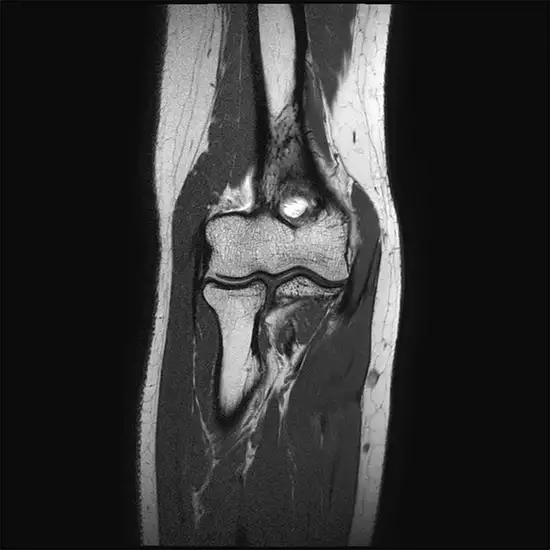

MRI (magnetic resonance imaging) Screening of the Arm with the Elbow is an imaging scan that uses strong magnets to create pictures of the upper and lower arm. This includes the elbow, wrist, and the surrounding muscles and other tissues.